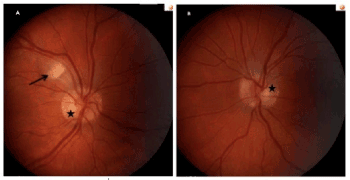

On examination, distance visual acuity was 20/20 in each eye with contact lenses. Ocular motility was full with no deviations, diplopia or nystagmus. Confrontation visual field was significant for a horizontal central scotoma in the right eye; it was full in the left eye. The pupils were round and reactive to the light; no anisocoria or relative afferent pupillary defect was detected. Intraocular pressure was 10 mmHg in each eye by applanation tonometry. Slit-lamp examination was unremarkable in either eye. Dilated fundus exam revealed marked right optic disc elevation with sharp margins and pink neuro-retinal rim, and an isolated cotton-wool spot adjacent to the supero-temporal vascular arcade (Figure 1). The left optic disc was notable for a mild elevation and blurriness of the nasal disc margin, with pink neuro-retinal rim throughout (Figure 1). The macula was unremarkable in either eye.

Figure 1. Color fundus photographs of the right eye (A) and the left eye (B). In the right eye, a fluffy cotton-wool spot adjacent to the superior temporal vascular arcade is seen (arrow). In each eye, buried optic disc drusen (asterisks) provide a typical pseudo-papilledema appearance.